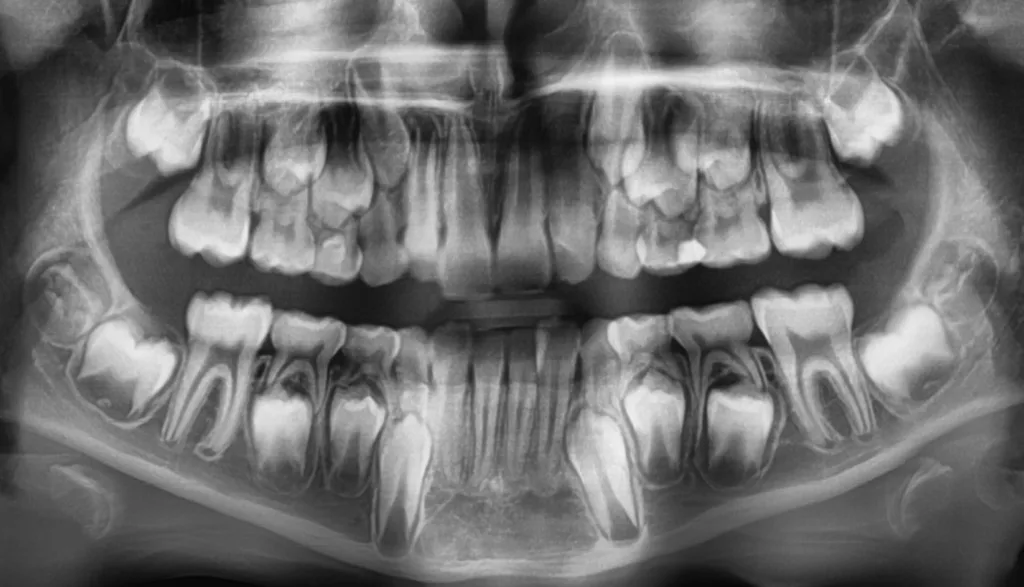

Bei routinemäßigen Röntgenkontrollen ergeben sich manchmal Zufallsbefunde unklarer Genese. So stellt sich beispielsweise bei der Betrachtung der Abbildung 1 die Frage, wie sich ein Zahnhartsubstanzdefekt so schnell entwickeln konnte. Ein weiteres Röntgenbild (Abb. 2), das vor dem Zahndurchbruch aufgenommen wurde, zeigt jedoch, dass es sich in diesem Fall nicht um Karies, sondern um die sogenannte präeruptive intrakoronale Resorption (PEIR) handelt. Für diesen Befund finden sich in der Fachliteratur auch noch andere Bezeichnungen wie „idiopathic external resorption of unerupted permanent teeth“ [1], „intra-follicular caries“ [2], „radiolucent lesions resembling caries“ [3], „occult caries“ [ 4] oder „pre-eruptive caries“ [5].

V. Slabkovskyi, O. LiutikovJahr vor dem Durchbruch des Zahnes 36.

Das fünfjährige Mädchen stellte sich 2017 zur jährlichen Routinekontrolle vor. Im Rahmen der Untersuchung wurden Röntgenaufnahmen der Milchmolaren gemacht (Abb. 2). Der klinische und radiologische Befund der vor uns früher gelegten Kompositfüllungen war gut, es wurde allerdings eine PEIR an den noch nicht durchgebrochenen ersten bleibenden Molaren festgestellt (Abb. 2). Den Eltern wurde empfohlen, sich unverzüglich bei Beginn des Durchbruchs der ersten Molaren erneut zur Behandlung vorzustellen. Ein Jahr später erschien die junge Patientin schmerzfrei zur Kontrolle. Der Zahn 36 war noch teilweise mit Gingiva bedeckt. Auf einer neuen Röntgenaufnahme (Abb. 1) wurde die PEIR-Läsion mit unveränderter Größe in pulpanahen Bereichen bestätigt (Grad 3 der Läsion nach Seow). Der Zahnschmelz sah intakt aus, es konnte kein pathologischer periapikaler Befund bei den noch nicht ausgewachsenen Zahnwurzeln festgestellt werden. Daraufhin wurden die verschiedenen Behandlungsmöglichkeiten von Fissurenversiegelung bis Vitalerhaltung der Zahnpulpa mit den Eltern des Kindes besprochen.

Unter Lokalanästhesie mit dem STA-System (Milestone Scientific, USA) und Septanest 1/200 000 (Septodont, Frankreich) wurde die überstehende Gingiva mit dem Khors Koagulator (Эctatex, Ukraine) koaguliert und der Bereich unter Kofferdam kontaminationsfrei dargestellt (Klammer U67, KSK Dentech, Japan). Die schmalen Fissuren wurden mit dem Fissurenbohrer CD-53F (Mani, Japan) erweitert, um anschließend mittels RONDOflex plus 360 (KaVo Dental, Deutschland) und Pulver 27 µm vollständig gereinigt werden zu können. Es konnte weder durch visuelle Inspektion noch Sondierung mit 0.08 H-file (Mani, Japan) ein Defekt des Zahnschmelzes festgestellt werden. Unter Berücksichtigung der Integrität des Zahnschmelzes, der Symptomlosigkeit, des Behandlungszeitpunktes, Alters des Kindes und Wachstums der Zahnwurzeln fiel gemeinsam mit den Eltern die Wahl auf eine konservative Therapie. Es wurde eine Fissurenversiegelung mit Clinpro Sealant (3M, USA) unter Anwendung eines adhäsiven Behandlungsprotokolls mit Optibond FL (Kerr, USA) durchgeführt. Dieser klinische Fall ist dahingehend einzigartig, da alle anderen ersten und zweiten Molaren des Kindes ebenso von einer PEIR betroffen waren (Grad 1 bis 2 der Läsion nach Seow) (Abb. 3 und 12). Normallerweise ist nur ein Zahn bei einer Patientin oder einem Patienten betroffen. Die Zahnkronen der anderen betroffenen Zähne erwiesen sich bei der klinischen Untersuchung als intakt; die radioluzenten Läsionen innerhalb des koronalen Dentingewebes waren wesentlich kleiner als die von Zahn 36. Daher wurde auch bei diesen Molaren das gleiche Behandlungsprotokoll angewendet und nur eine Fissurenversiegelung durchgeführt.